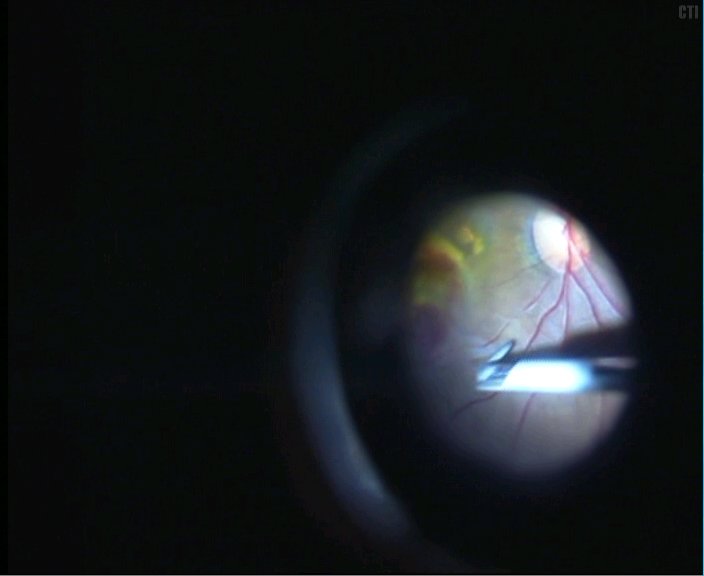

1、术前可见黄斑下血管膜机化渗出

2、黄斑区下方剪开视网膜